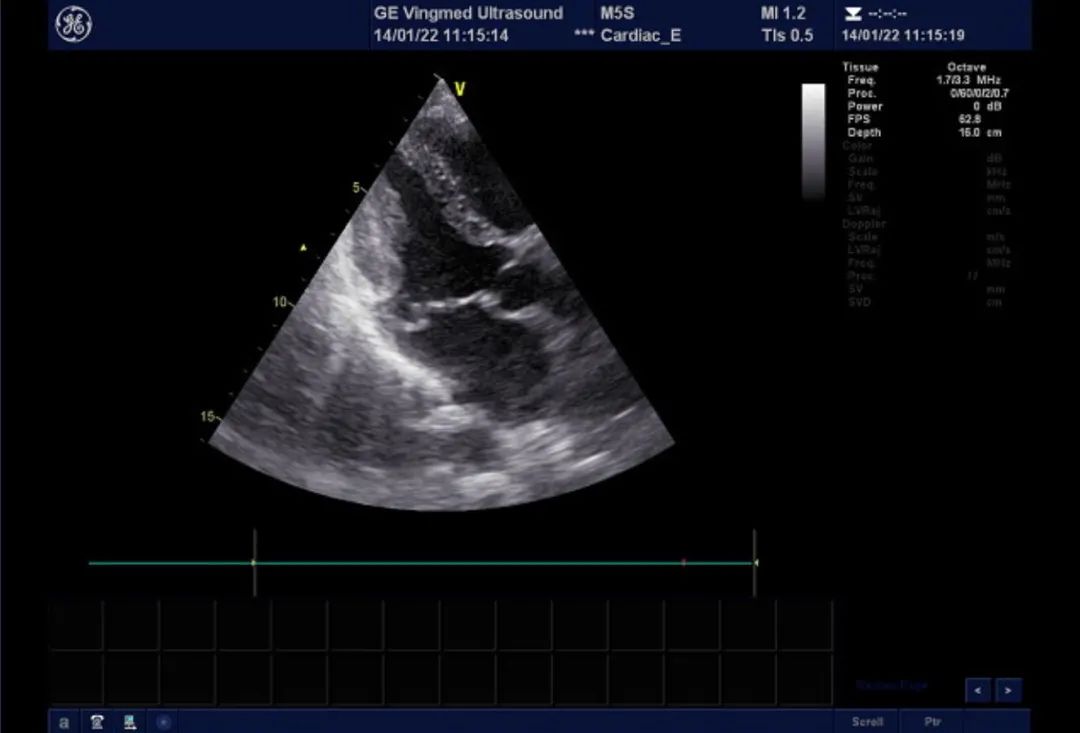

心脏超声:AO:26mm, IVSd: 8mm, LVDd:44mm, FS:43%,HR:84BPM LA:39mm, LVPWd:8mm, LVDs:25mm, LVEF:74%,RV:36mm M型、2-DE:左房饱满,大小约45*55mm,左室大小正常范围,右心增大,右房大小约44*51mm,升主动脉不宽,主波明显,重搏波清晰,主瓣清晰,启闭无殊;二尖瓣增粗、增强,后叶收缩期凸向左房,P2区为主。室壁不厚,室间隔与左室后壁逆向运动。肺动脉主干内径21mm。静息状态下各切面未见室壁节段性运动异常。房间隔可见两处回声中段,孔1位于近十字交叉处,宽约11mm,十字交叉残端不明显。孔2位于房间隔中段,宽约9mm。三尖瓣瓣环内径约38mm。超声诊断先天性心脏病,房间隔缺损(继发孔型,双孔型考虑),二尖瓣后叶脱垂伴关闭不全(P2区为主,中重度)。

二尖瓣后叶脱垂,大量返流

双孔型房缺,分别为1cm及8mm大